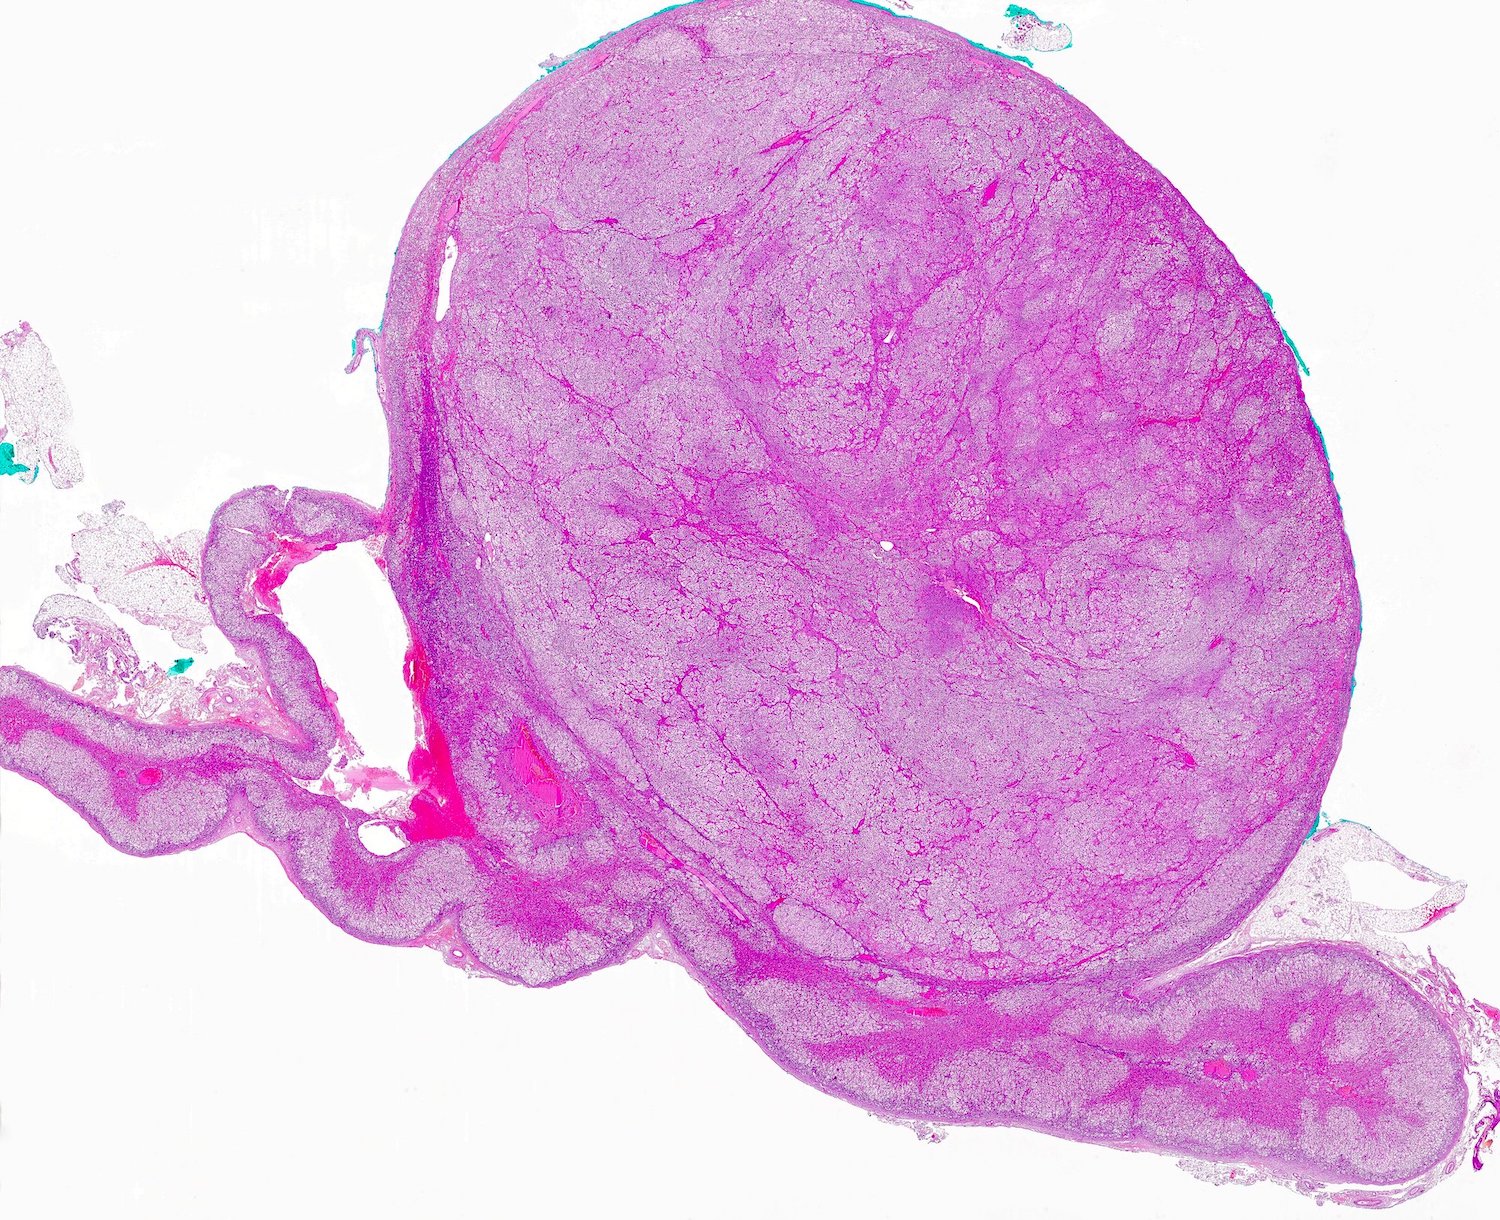

Gross description

- Weight usually < 50 grams (in pediatric patients may weight up to 500 grams) (Mod Pathol 2011;24:S58)

- Size usually < 5 cm

- Unilateral, solitary, golden yellow

- May have focal dark areas corresponding with hemorrhage, lipid depletion, increased lipofuscin

- Functional adenoma may result in atrophy of ipsilateral or contralateral adrenal cortex

Gross images

Microscopic (histologic) images

Contributed by Xiaoyin "Sara" Jiang, M.D., Debra Zynger, M.D., @Andrew_Fltv on Twitter and @SueEPig on Twitter